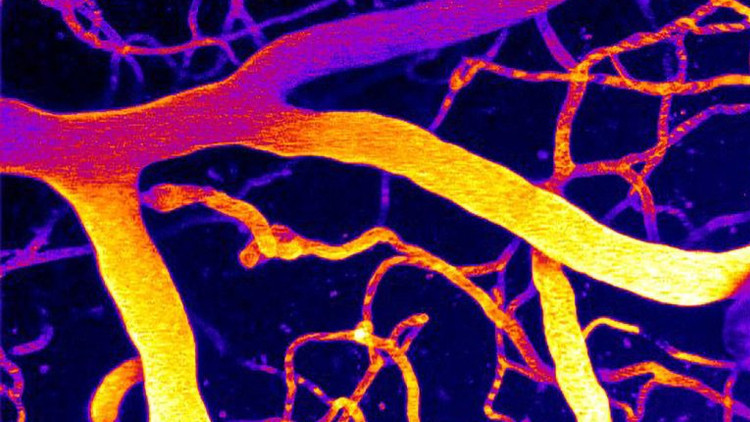

Beyin damarlarını döşeyen hücreler, kanın akışına göre damar çapını anlık olarak ayarlamak zorunda. Bu ayarlama, beynin farklı bölgelerinin “o anki ihtiyacı”na göre daha fazla ya da daha az kan almasını sağlıyor. Piezo1 ise bu sistemde bir tür basınç/gerilim sensörü gibi çalışıyor: Kandan gelen mekanik kuvvetleri algılıyor ve hücrelerin verdiği yanıtın parçası oluyor. Çalışmaya göre, Alzheimer gibi durumlarda Piezo1’in aktivitesi gereğinden fazla yükseldiğinde, bu hassas ayar mekanizması sağlıklı biçimde işlemez hale gelebiliyor.

Demans denince çoğu kişinin aklına ilk olarak protein birikimleri, iltihap süreçleri ve sinir hücrelerindeki hasar geliyor. Bu çalışma ise “damar tarafı”na güçlü bir projektör tutuyor: Beynin sağlıklı çalışabilmesi için yalnızca nöronların değil, onları besleyen damar ağının da doğru çalışması gerekiyor. Kan akışındaki kronik bozulmalar, enerji ve oksijen dengesini etkileyerek bilişsel işlevlerdeki düşüşe zemin hazırlayabiliyor. Bu yüzden beyin dolaşımını düzeltmeye yönelik hedefler, demans araştırmalarında giderek daha fazla önem kazanıyor.